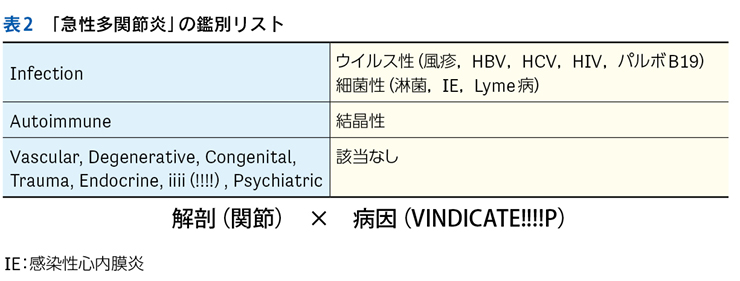

▶ 再びNew England Journal of Medicine誌上の症例検討3)を例として挙げる。40歳代男性が急性多関節炎,下腿の結節性紅斑,両側肺門部リンパ節腫脹を呈したケースである。これら3個の問題の組み合わせは,知っていればLöfgren症候群というサルコイドーシスの1病型と「スナップ診断」できるが,この知識がなくてもフレームの重ね合わせで診断に至ることが可能である。

▶ これらの問題はそれぞれが比較的high yieldであり,よいフレームとなりうる。3つのフレーム内でそれぞれ網羅的に鑑別を挙げ(その方法はステップ②で後述),重なるところに着目するとサルコイドーシスが診断の第一仮説に浮上する。ちなみにこのケースでは患者は発熱と失神も呈しているが,発熱はlow yieldであり鑑別を減らすのに役立たず(急性多関節炎,結節性紅斑,肺門部リンパ節腫脹を呈する疾患はほぼすべて発熱を呈してもおかしくない),失神はこのケースでは最終的に(心サルコイドーシスに起因するものではなく)発熱下での神経調節性失神という評価となり,サルコイドーシスの診断においてはノイズだった(二元論で説明される症状だった)ことがわかる(図7)。